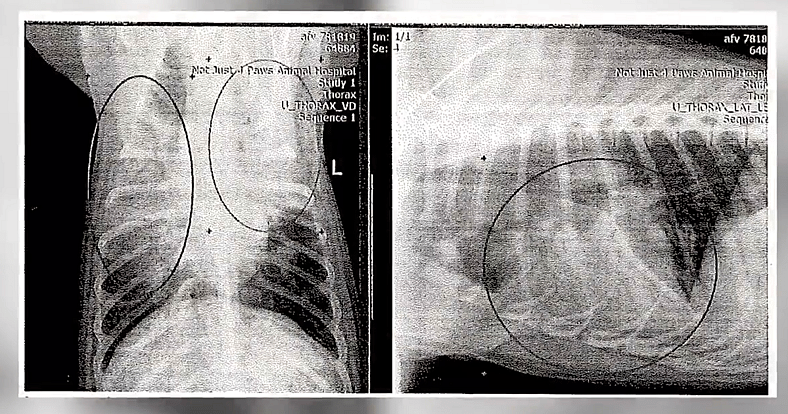

He had stopped eating, developed a fever, and his breathing became labored. The shelter didn’t have a full-time vet on staff, so I stepped in to get him the help he needed. My friend Phil transported Dylan to a veterinary clinic—not an emergency hospital, but the situation was serious. There, he was diagnosed with aspiration pneumonia. The vet confirmed significant inflammation, likely from long-term neglect.